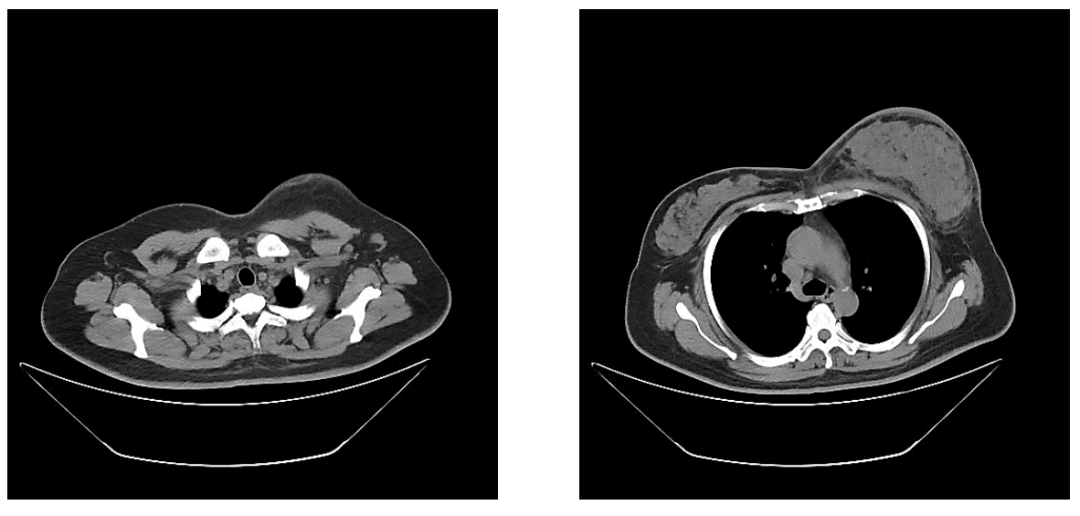

胸部CT平扫提示两肺部纹理清晰,未见确切异常密度影。纵隔内未见确切淋巴结肿大。双侧胸膜未见明显增厚,双侧胸腔未见积液。左乳明显增大,腺体弥漫性致密,左腋下见多发肿大淋巴结影,短径约1.3cm(图3)。

图3.胸部CT平扫

新辅助治疗6周期后再次CT评估,提示两肺未见明显异常密度影。纵隔内未见确切肿大淋巴结。双乳腺体致密,左乳局部可见点状高密度影,未见确切异常强化灶;双侧腋窝未见明显肿大淋巴结(图9)。

图9.新辅助治疗6周期后胸部CT平扫(箭头处提示金属clip位置)